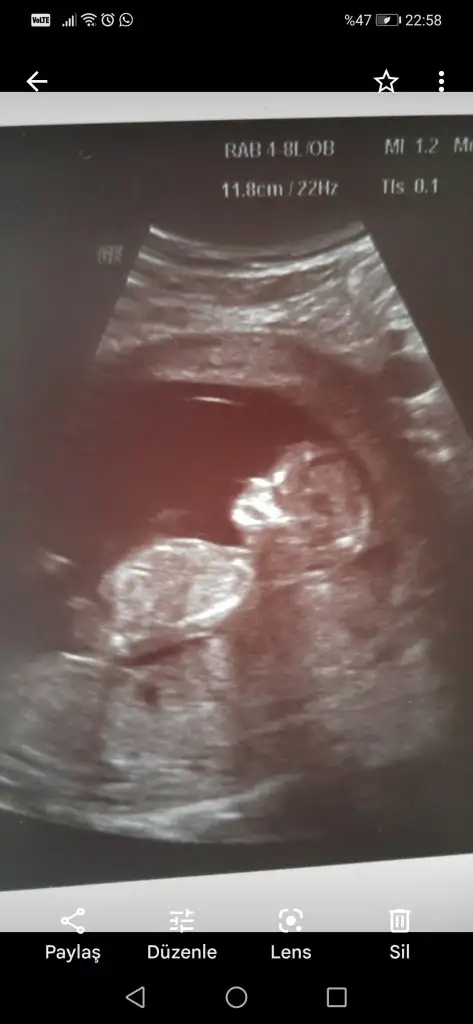

Bir de ultrason" deseniz.Neyse,utrasyon degil en azindan:)Selam Kızlarbir çok kişi gruplardan beni bilir. Yine yetiştim imdatlara

Çoook uzun bir süre araştırma okuma yaptıktan sonra sizlere bu başlığı açtım çevremde tüm gebelere de denedim. Bunun sırrını çözen İnstagramda (isim vermeyim) işi ticarete dökmüş bile.Nub, Ramzi,Çin Rus Japon Takvimleri, Yüzük Yöntemi bir çok şey size sayabilirim.

5 ve 14. haftaya kadar olan ultrasyon fotolarınızı paylaşın. Vajinadan mı yoksa karından mı çekildiğini ve kaç haftalık olduğunu da mutlaka belirtin.

Not: Tahmin yaptığım anneler cinsiyet öğrendikten sonra lütfen bana geri dönüş yapın![]()